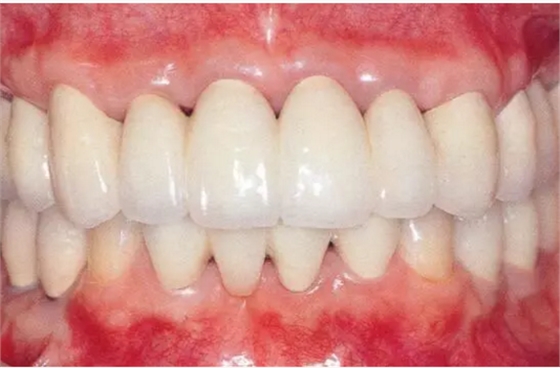

33333.png

▲圖19-13

佩戴最終修復(fù)體時的正面照片。